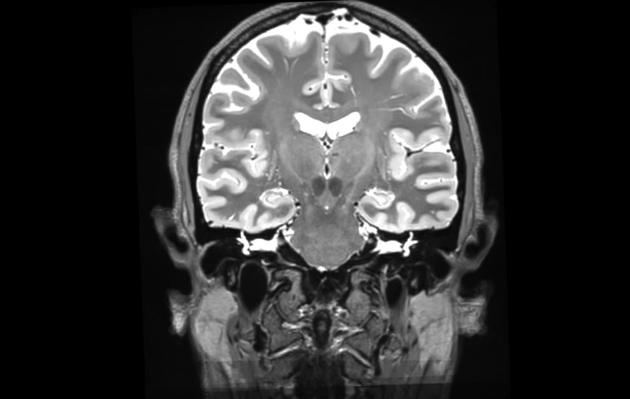

An fMRI scan of Dr. Russell Poldrack's brain, taken as part of his 18-month study.

Stanford University neuroscientist Russell Poldrack is the proud owner of the most studied brain in the world.

During an 18-month period, Poldrack underwent a 10-minute fMRI scan every Tuesday and Thursday morning, and took weekly blood samples to analyze gene expression.